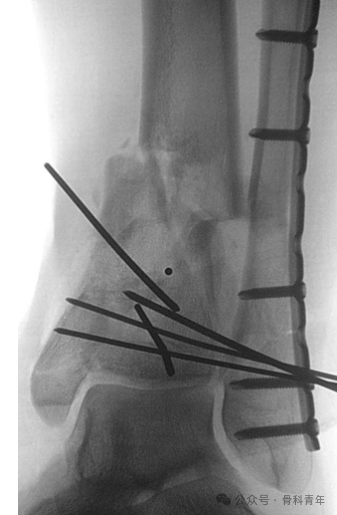

固定(Span):实施跨关节外固定架固定术;

扫描(Scan):进行 CT 检查,包括三维重建;

规划(Plan):制定确定性骨折内固定手术方案,包括患者体位、手术入路、复位方法、手术器械和内植物的选择等

腓骨骨折的固定